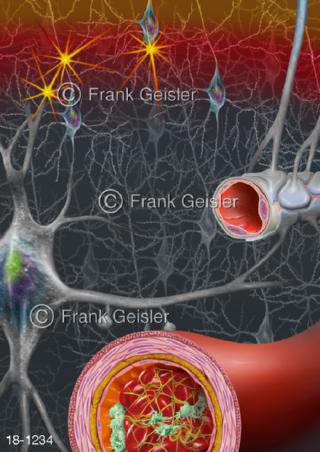

18-1234 Ischämischer Schlaganfall Hirninfarkt